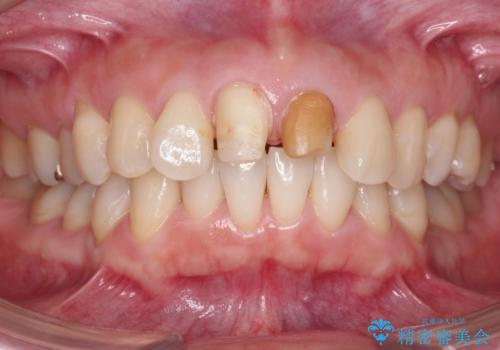

変色した前歯をセラミックでひっこめたい

- 前歯の色と、前突感を気にして来院。

全体的な矯正治療をすすめましたが、ご希望されませんでした。

左上の前歯の神経が失活(死んでいた)していたため、神経の治療を行いました。

また、右上の前歯を下げるため、便宜的に神経を取る治療を行いました。